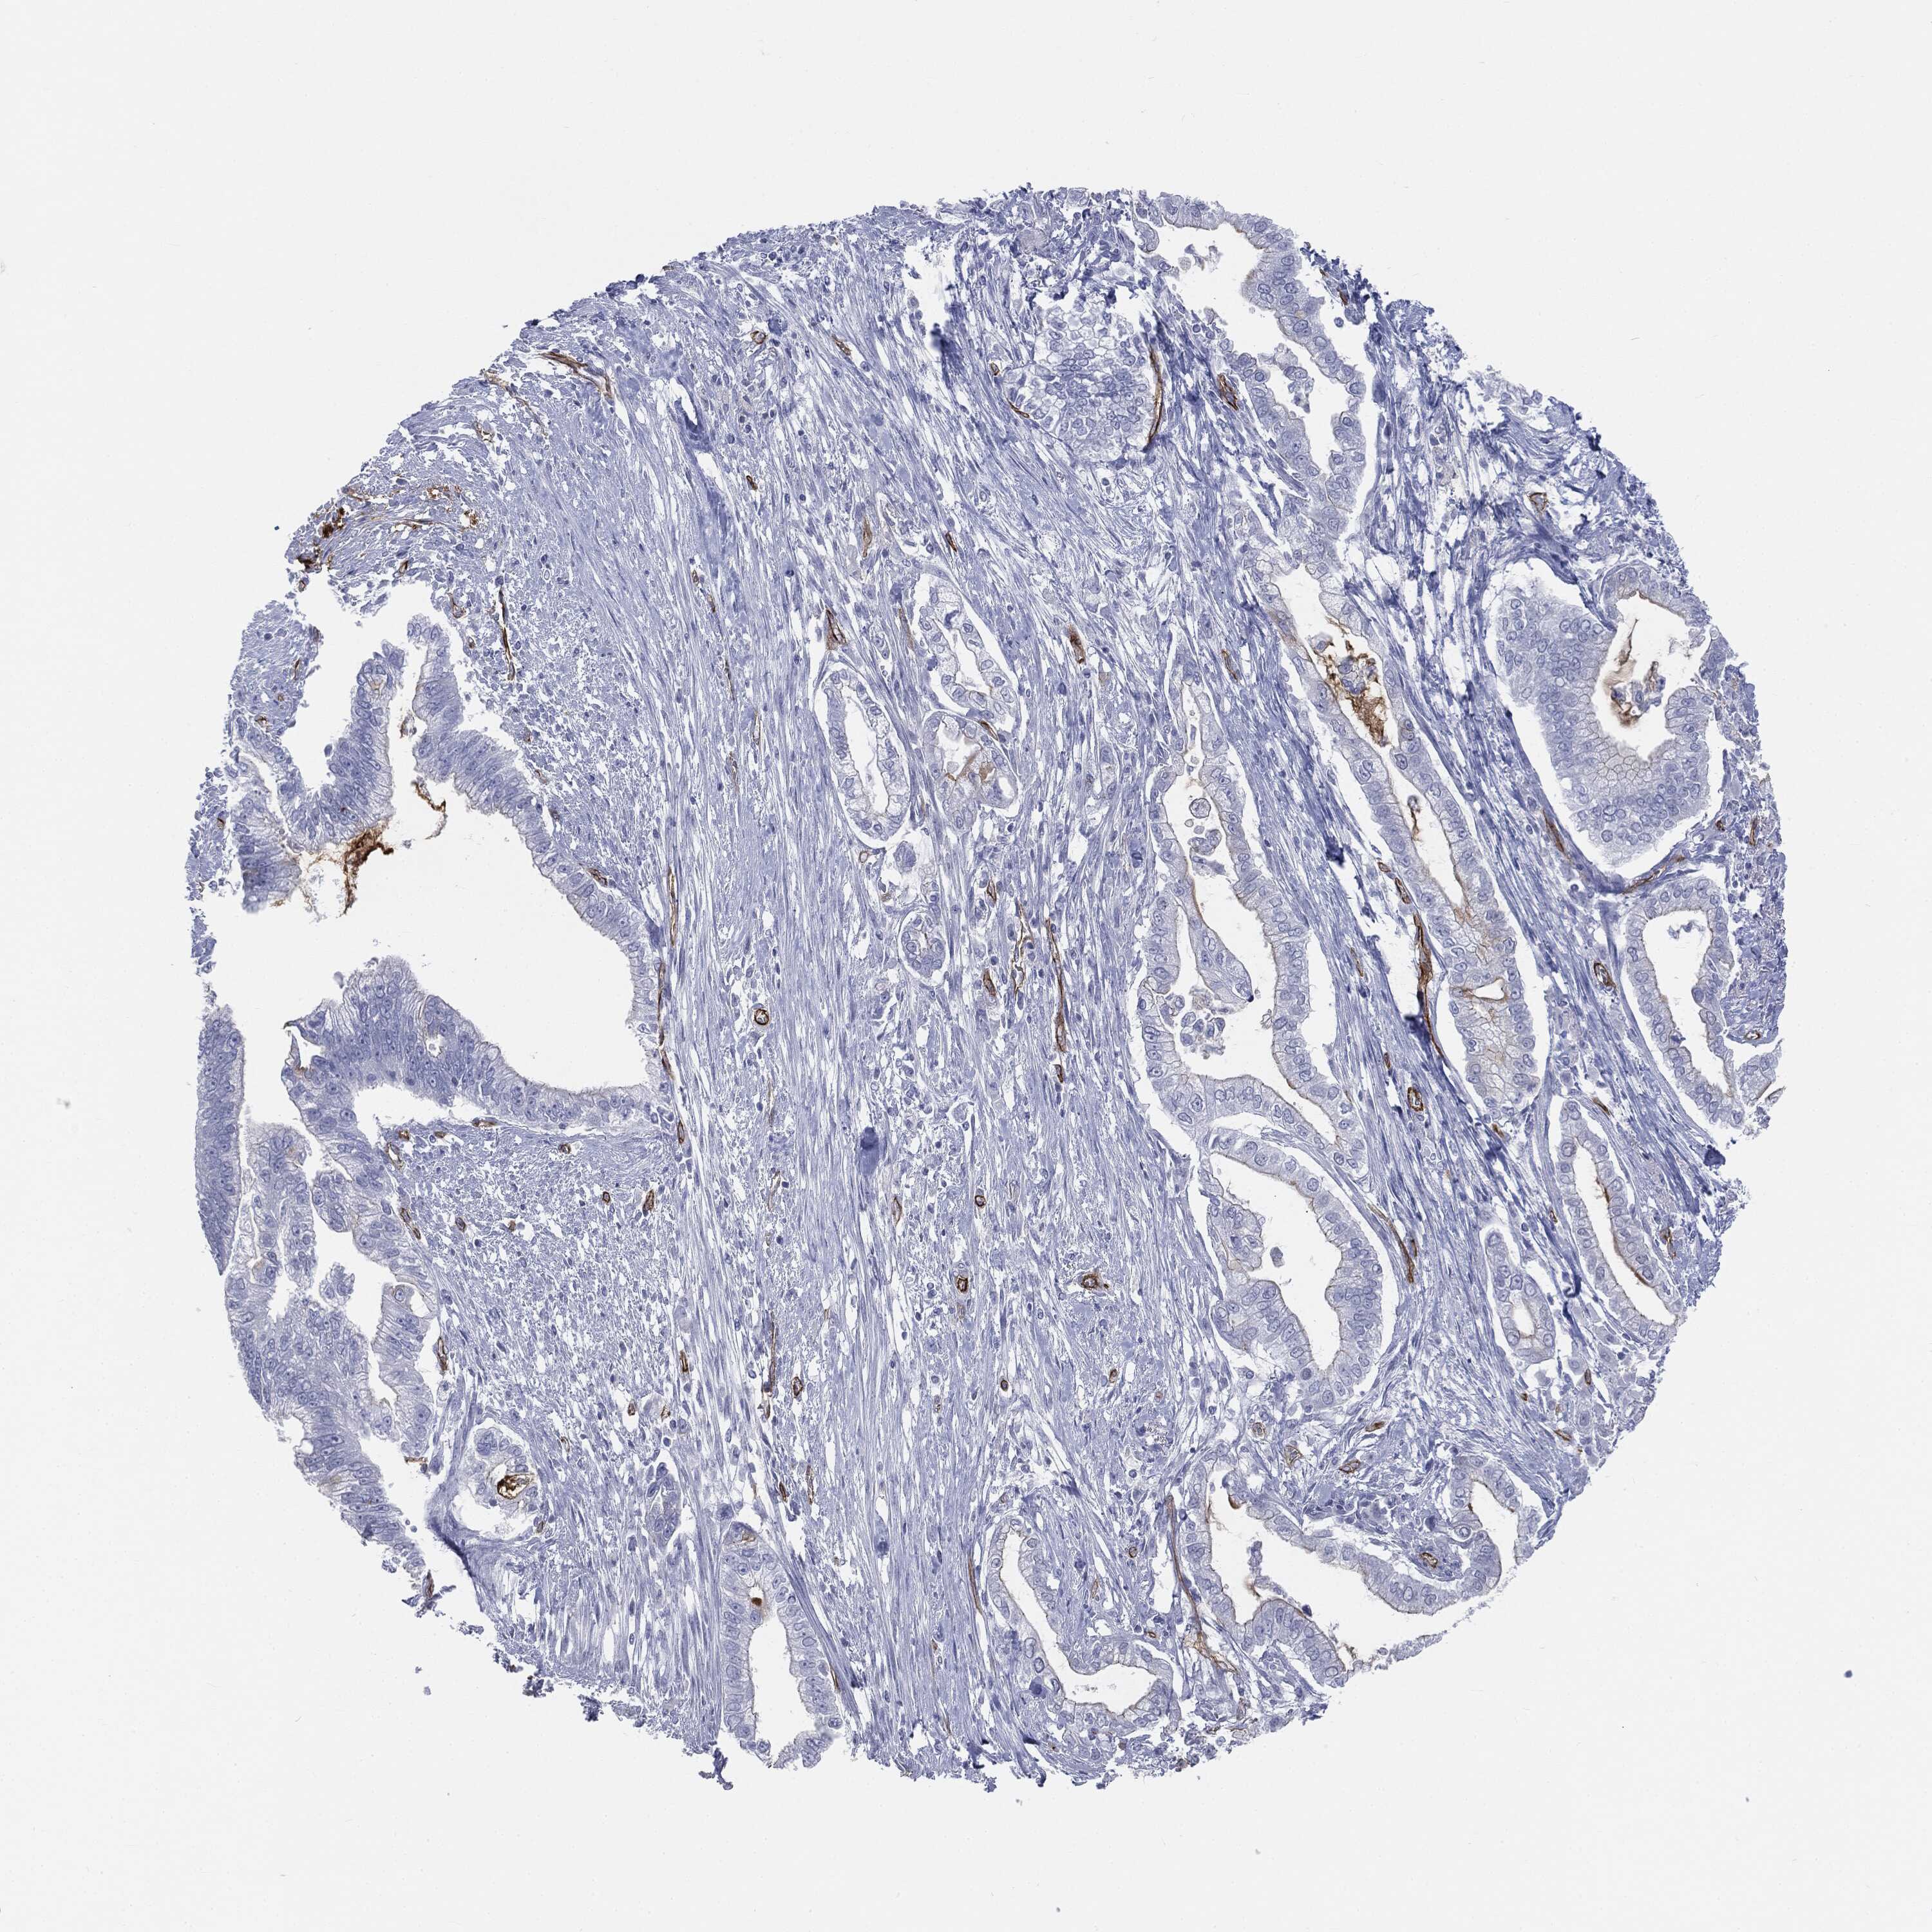

PANCREATIC CANCER - Protein expressioni

A mouse-over function shows sample information and annotation data. Click on an image to view it in a full screen mode. Samples can be filtered based on level of antibody staining by selecting one or several of the following categories: high, medium, low and not detected. The assay and annotation is described here.

Note that samples used for immunohistochemistry by the Human Protein Atlas do not correspond to samples in the TCGA dataset.

Antibody stainingi

Antibody staining in the annotated cell types in the current human tissue is reported as not detected, low, medium, or high, based on conventional immunohistochemistry profiling in selected tissues. This score is based on the combination of the staining intensity and fraction of stained cells.

Each image is clickable and will lead to virtual microscopy that enables deeper exploration of all samples and also displays staining intensity scores, fraction scores and subcellular localization as well as patient and tissue information for each sample.

Adenocarcinoma, NOS

Adenocarcinoma, metastatic, NOS